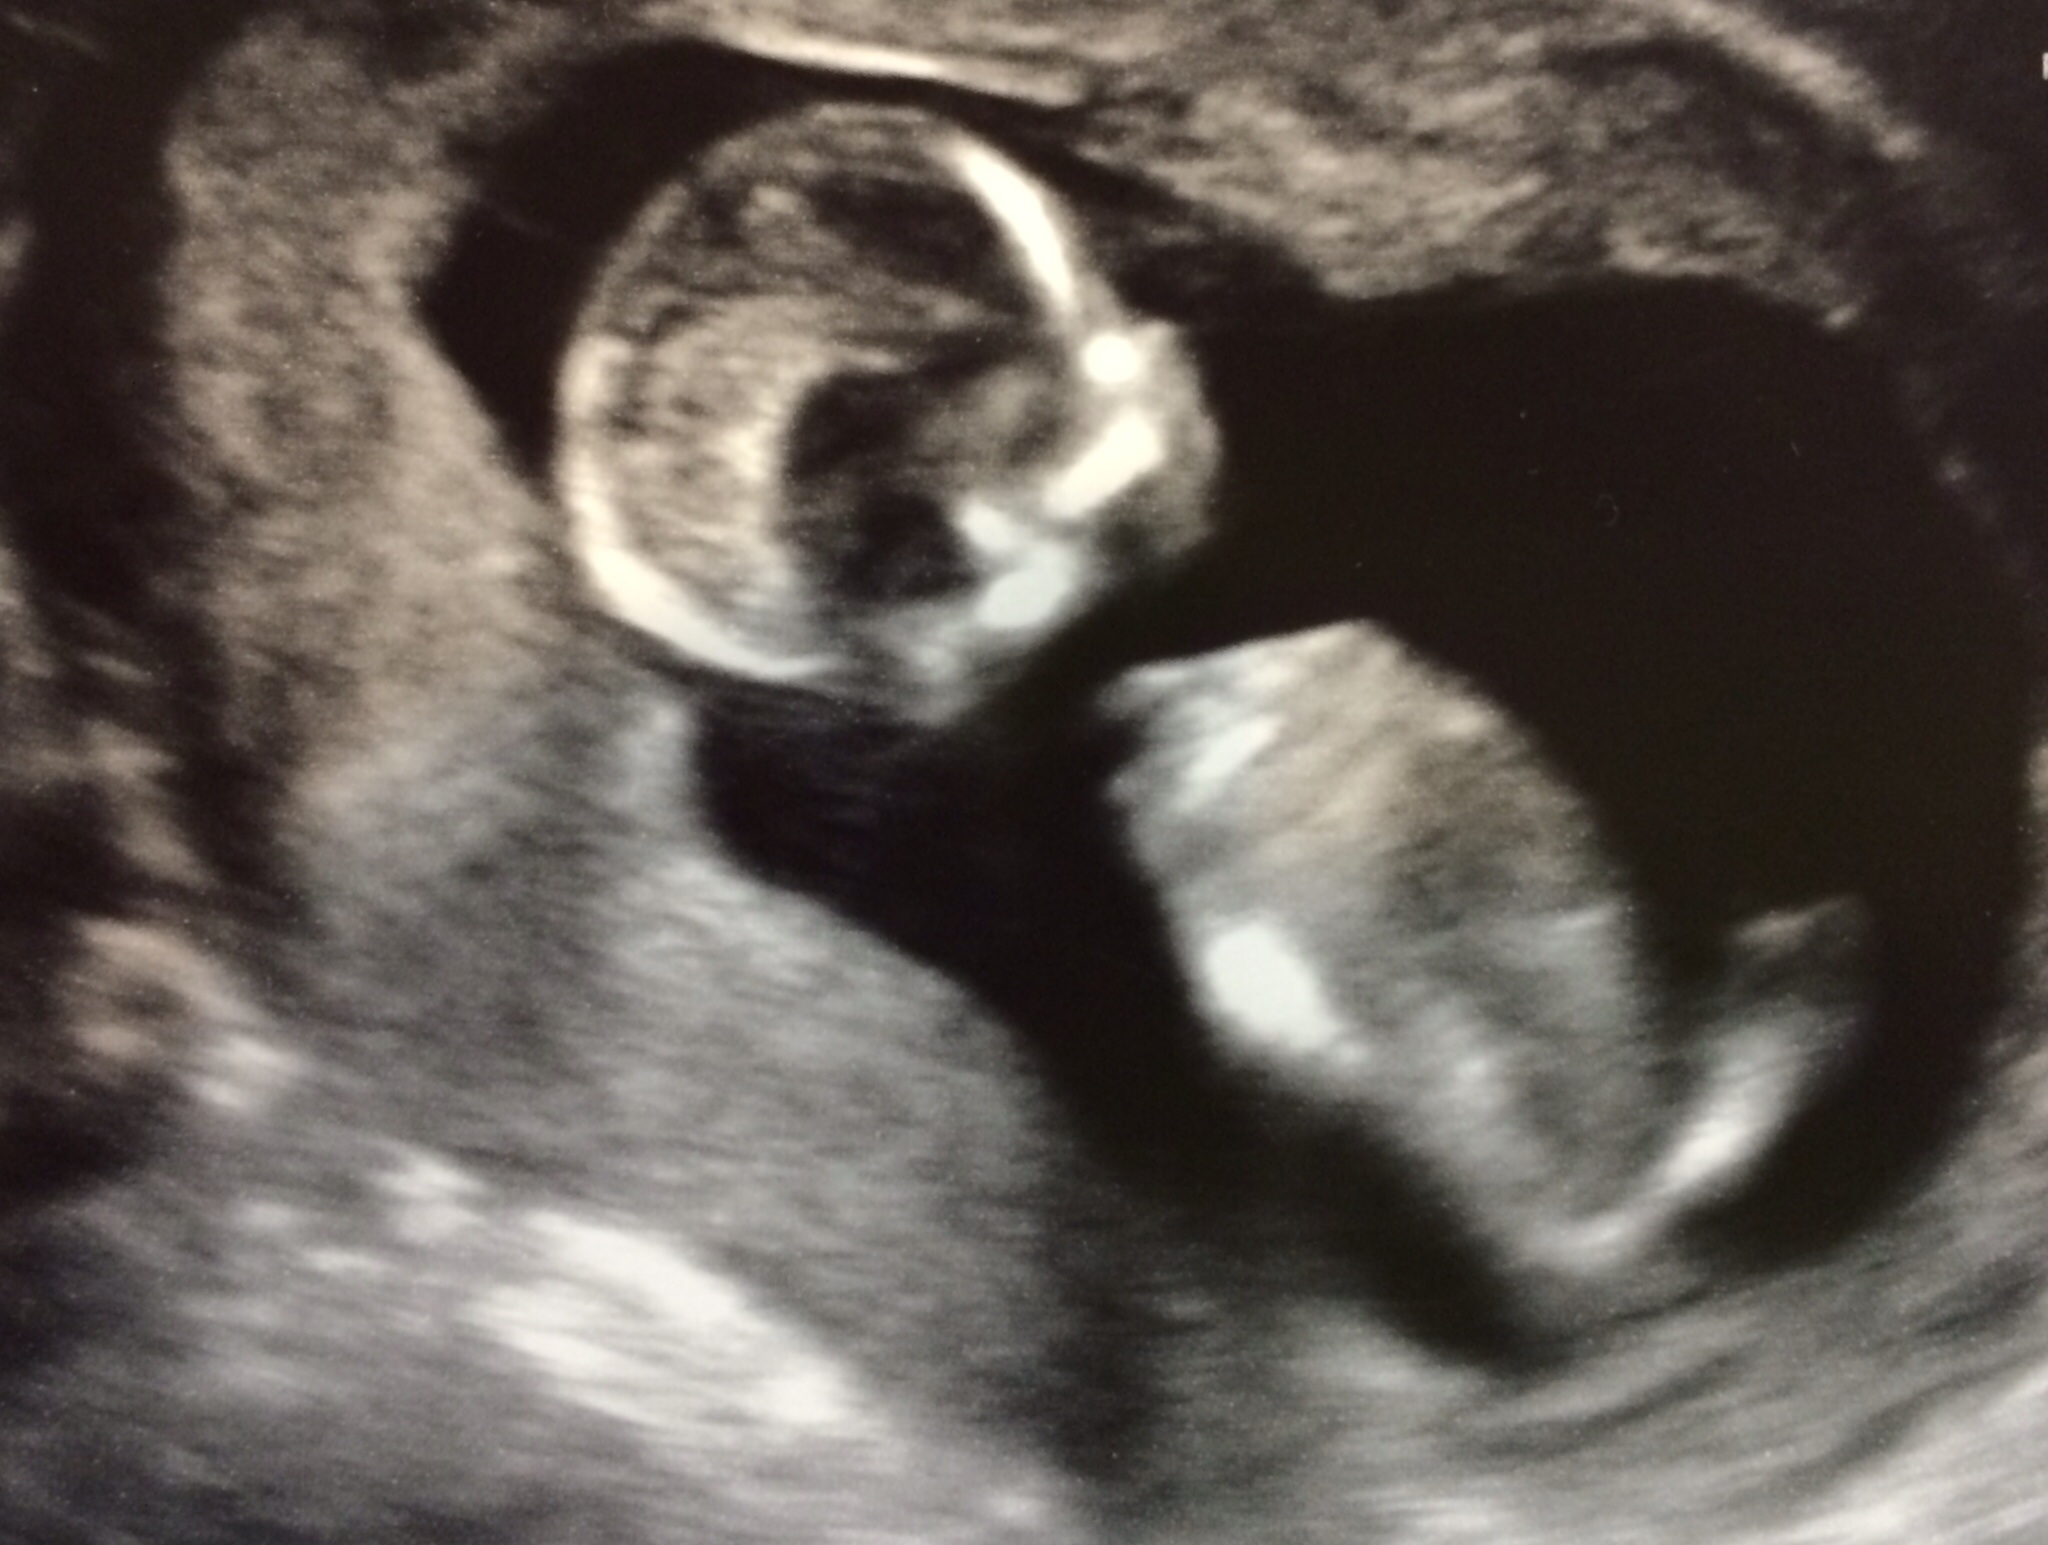

• I don't know what the skull theory is but that thing at the bottom of the torso could totally be a penis. It's probably a leg but could be a penis. I'm guessing boy

• So...your scan is next week. Does this mean we are looking at a 12 -14 week ultrasound? You do know that regardless of what theory you want to use that at that age they aren't distinguishable on an ultrasound? If not please let us know and we can send you a link....or you could Google.

Now since you probably meant this a light hearted and fun post I will give you my guess....puppy!

• Your baby does appear to have a skull. That's a good sign.

This is my baby!

The voldemort style lack of nose of your baby made me jump! Ahhh scary alien babe